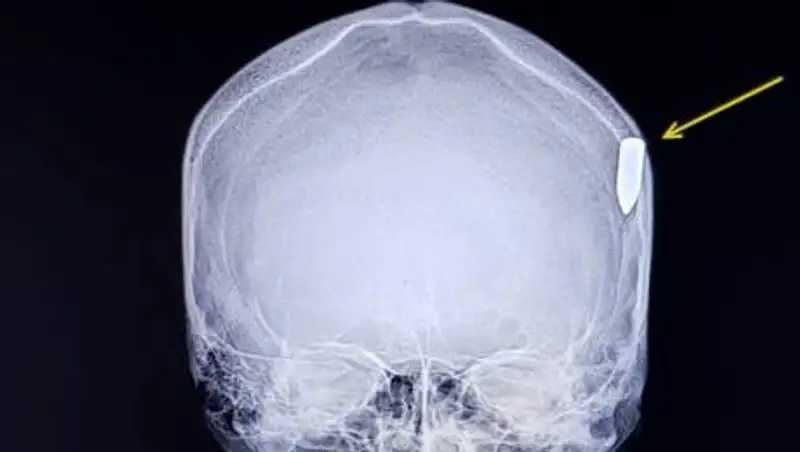

Пострадавшего доставили травматологическое отделение Мангистауской областной больницы. На снимке МРТ видно, что в голову "попал" объект похожий на пулю.

В Актау военнослужащий срочной службы воинской части 3502 рядовой Каримов А. получил непроникающее пулевое ранение в голову. В данный момент солдат находится в больнице. Состояние - стабильное, без угрозы здоровью, - прокомментировали инцидент в пресс-службе Национальной гвардии РК.